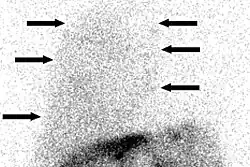

| Chest X-ray showing a hepatic hydrothorax in a person with cirrhosis | |

Hepatic hydrothorax is a rare form of pleural effusion that occurs in people with liver cirrhosis. It is defined as an effusion of over 500 mL in people with liver cirrhosis that is not caused by heart, lung, or pleural disease. It is found in 5–10% of people with liver cirrhosis and 2–3% of people with pleural effusions. In cases of decompensated liver cirrhosis, prevalence rises significantly up to 90%.[1] Over 85% of cases occurring on the right, 13% on the left, and 2% on both.[2] Although it is most common in people with severe ascites, it can also occur in people with mild or no ascites. Symptoms are not specific and mostly involve the respiratory system.